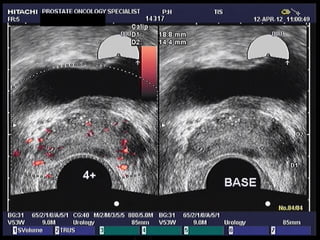

Color Doppler Ultrasound

• Accurately determines prostate size

• Detects hypo-echoic and hyper-vascular areas

that can be monitored with sequential scans

or targeted with biopsy

• A fifteen-minute outpatient procedure

Color Doppler Ultrasound •Accurately determines prostate size • Detects hypo-echoic and hyper-vascular areas that can be monitored with sequential scans or targeted with biopsy • A fifteen-minute outpatient procedure performed in the doctor’s office